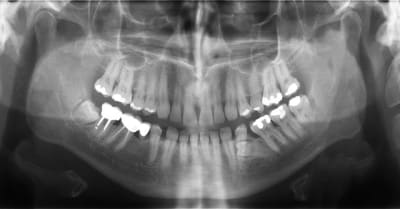

ou alors prémolaires inférieures incluses ? a priori tori mandibulaire

une radio ?

ceux sont bien des tori mandibulaires, mais avec option dent incluse.